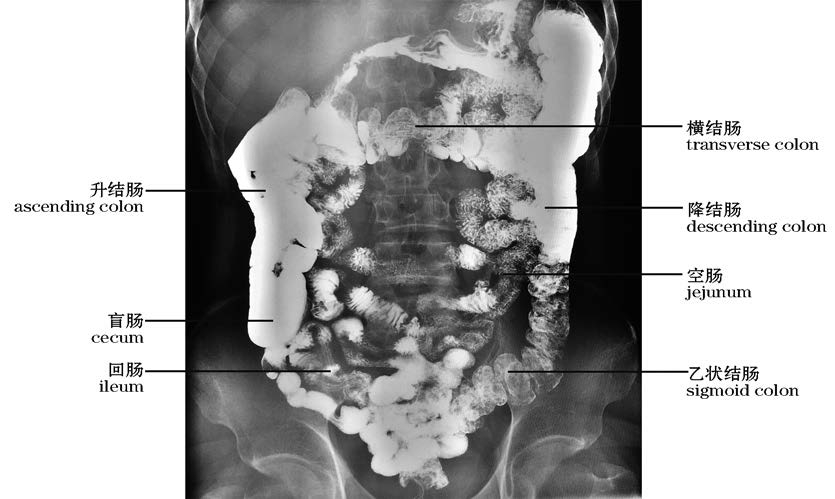

图4-50 下消化道钡剂造影

Barium radiographs of the lower gastrointestinal tract